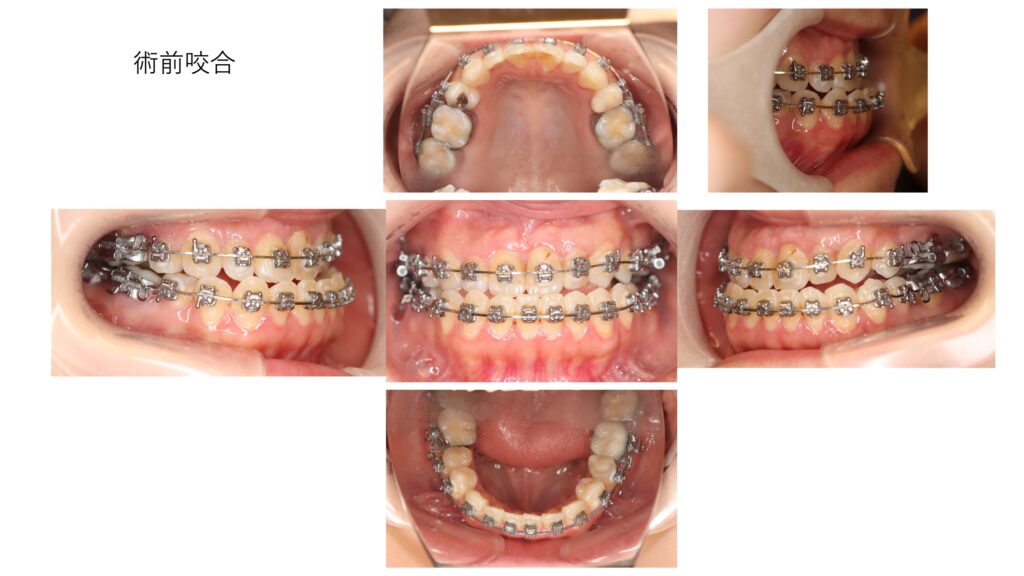

下顎前突(受け口)の改善を希望して、受診された患者さんの治療経過を紹介します。

術後6ヶ月の咬合です。反対咬合から正常な咬合に変化しています。